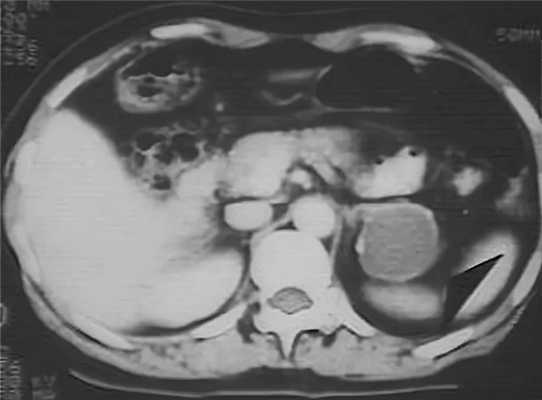

![КТ ОБП/ЗП. Аденомы обоих надпочечников.]()

Гормональную активность опухоли надпочечников можно оценить, используя селективную надпочечниковую флебографию - рентгенконтрастную катетеризацию надпочечниковых вен с последующим забором крови и определением в ней уровня гормонов. Исследование противопоказано при феохромоцитоме, т. к. может спровоцировать развитие криза. Размеры и локализацию опухоли надпочечников, наличие отдаленных метастазов оценивают по результатам УЗИ надпочечников, КТ или МРТ. Эти диагностические методы позволяют выявить опухоли- инциденталомы диаметром от 0,5 до 6 см.